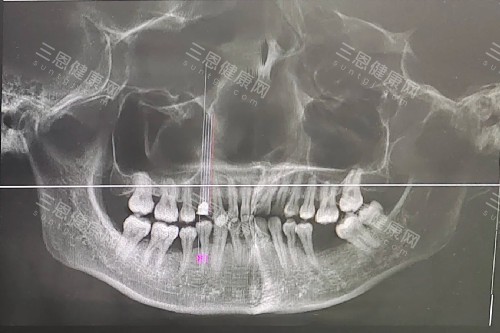

缺牙修復怎麼選?種植、活動、吸附性義齒對比的口腔條件要求不一樣。種植牙需要牙槽骨有一定厚度,要是牙槽骨薄,得先植骨(單顆植骨費 5000-8000 元),還不能有重度的牙周炎;

活動義齒對口腔條件要求比較低,就算牙槽骨重度萎縮、有輕微牙周炎也能做,不用額外治療;吸附性義齒對牙槽骨要求比活動義齒稍高,不能完全沒有牙槽骨支撐,但不用植骨,缺牙修復怎麼選?種植、活動、吸附性義齒對比的口腔條件,決定了自己能做哪種。

比如牙槽骨重度萎縮的老人,做不了種植牙,選活動義齒更適配;牙槽骨有點薄但不用植骨的人,不想做種植牙,選吸附性義齒更穩,缺牙修復怎麼選?種植、活動、吸附性義齒對比的口腔條件,是選修複方式的前提。